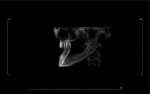

The 45-year-old female patient presented seeking a replacement for an unsatisfactory maxillary denture that she had received 2 years earlier, after extraction of her last remaining maxillary teeth (Figure 1). A smoker, she underwent clinical and radiological examination that revealed bilateral sinus pneumatization. Her premaxilla was angled, with a pronounced buccal undercut. A computed tomographic (CT) scan confirmed the buccal concavity and the slope of the premaxilla (Figure 2).

Although the ridge width was sufficient to accommodate narrow-diameter implants to support an overdenture, placing such implants to follow the long axis of the triangle of bone would have created excessive buccal lip contours. To correct the buccal concavity, a ridge-splitting procedure or augmentation with bone-graft particulate and tent screws was recommended. However, the patient declined, citing financial limitations.

Immediately after implant placement, a panoramic radiograph was taken (Figure 11). It confirmed that none of the implants were impinging on the sinus cavity. A postsurgical CT scan (Figure 12) confirmed that placement of the 20-degree angled implants followed the natural slope of the maxillary ridge, creating adequate prosthetic space.